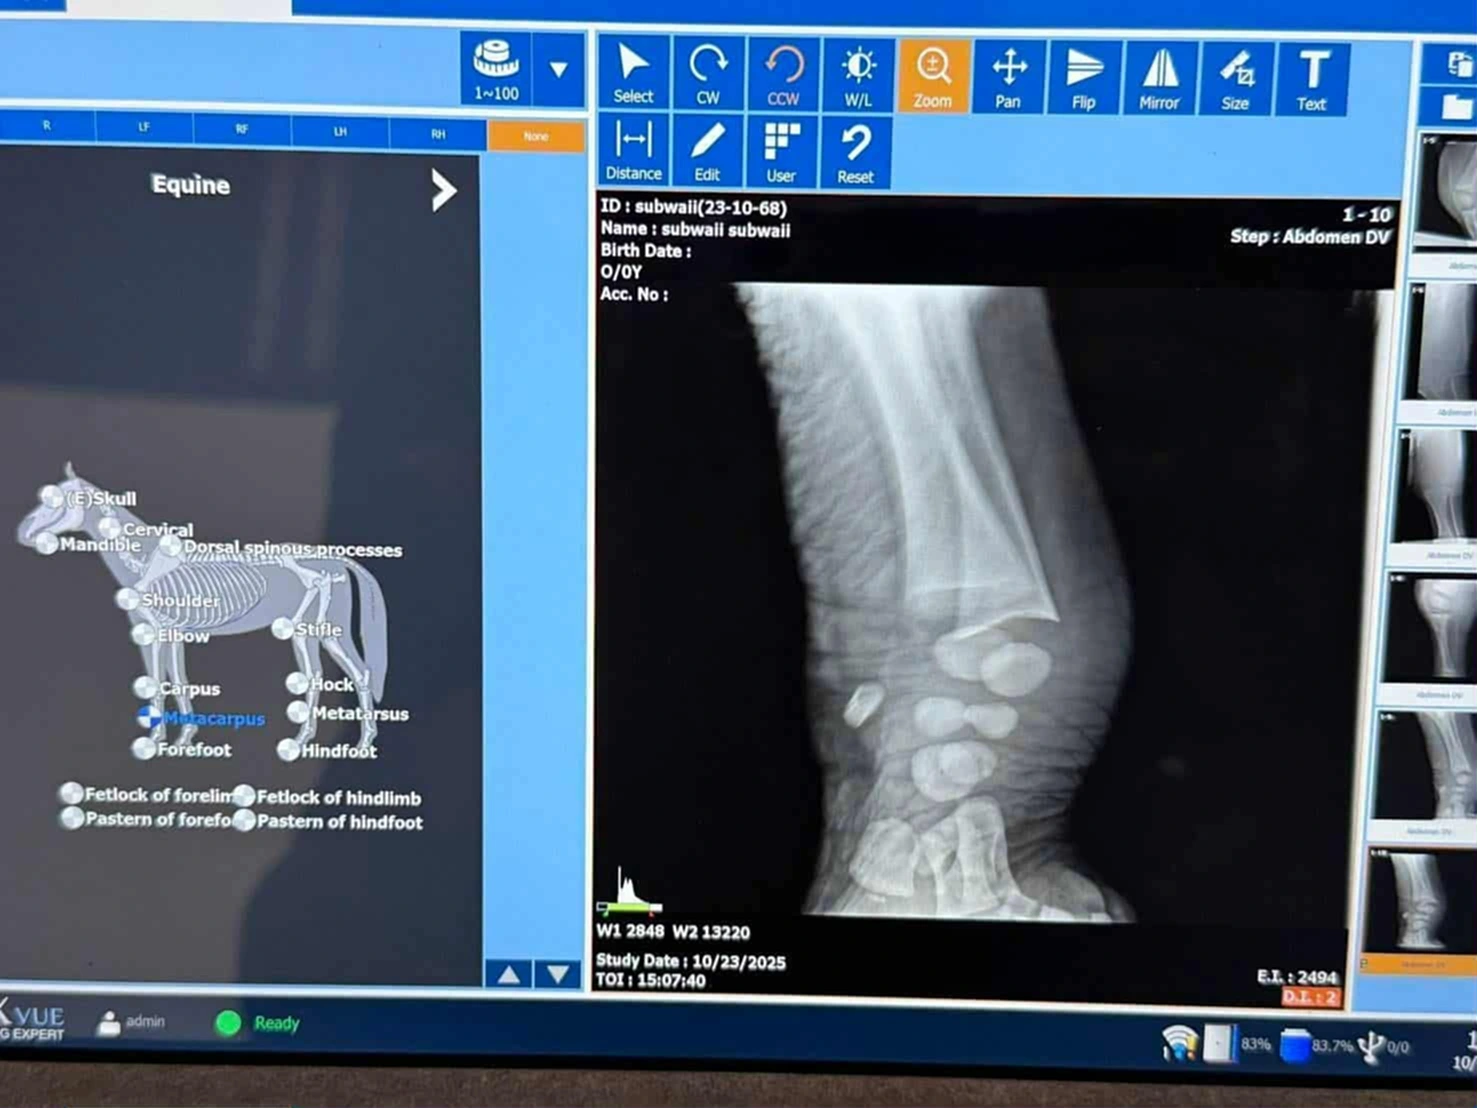

ต่อมาในวันนี้ (23 ต.ค.) ทีมสัตวแพทย์ สบอ.7 (นครราชสีมา) ร่วมกับศูนย์ช่วยเหลือสัตว์ป่าที่ 2 (กระบกคู่) ทำการรักษาตรวจวินิฉัยโรค ดังนี้ 1.ชั่งน้ำตัวช้างป่าได้ 131 กก. วัดความสูง 100 ซม. 2.ถ่าย X-RAYs ขาหน้าซ้ายและขาหลังขวา ที่มีอาการบวมและเจ็บขา ปรากฏไม่พบความผิดปกติของกระดูกและข้อ 3.การรักษาได้ให้ยาลดปวดอักเสบและล้างแผล 4.เจาะเลือดเพื่อส่งตรวจห้องปฎิบัติการ 5.ลูกช้างป่ามีสภาพตื่นตัวดี กินนมได้ปริมาณน้อย พบแผลในช่องปาก